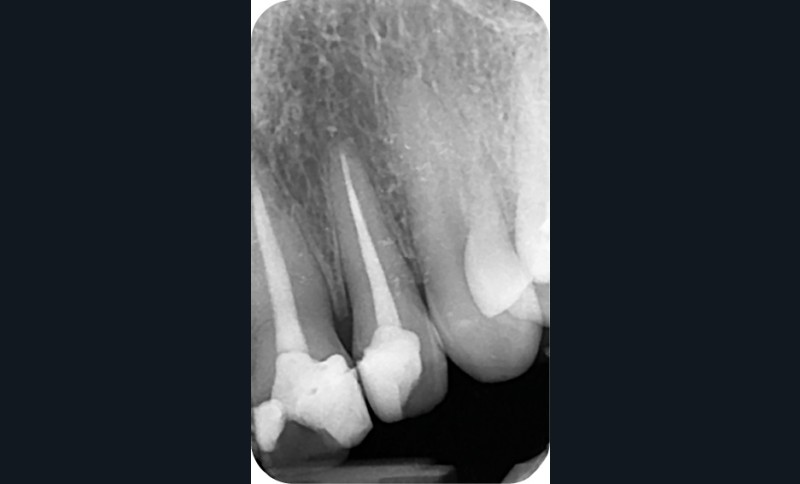

– Iatrogène (à la suite de traitements endodontiques ou à l’amalgame d’argent) (fig. 6a, b).